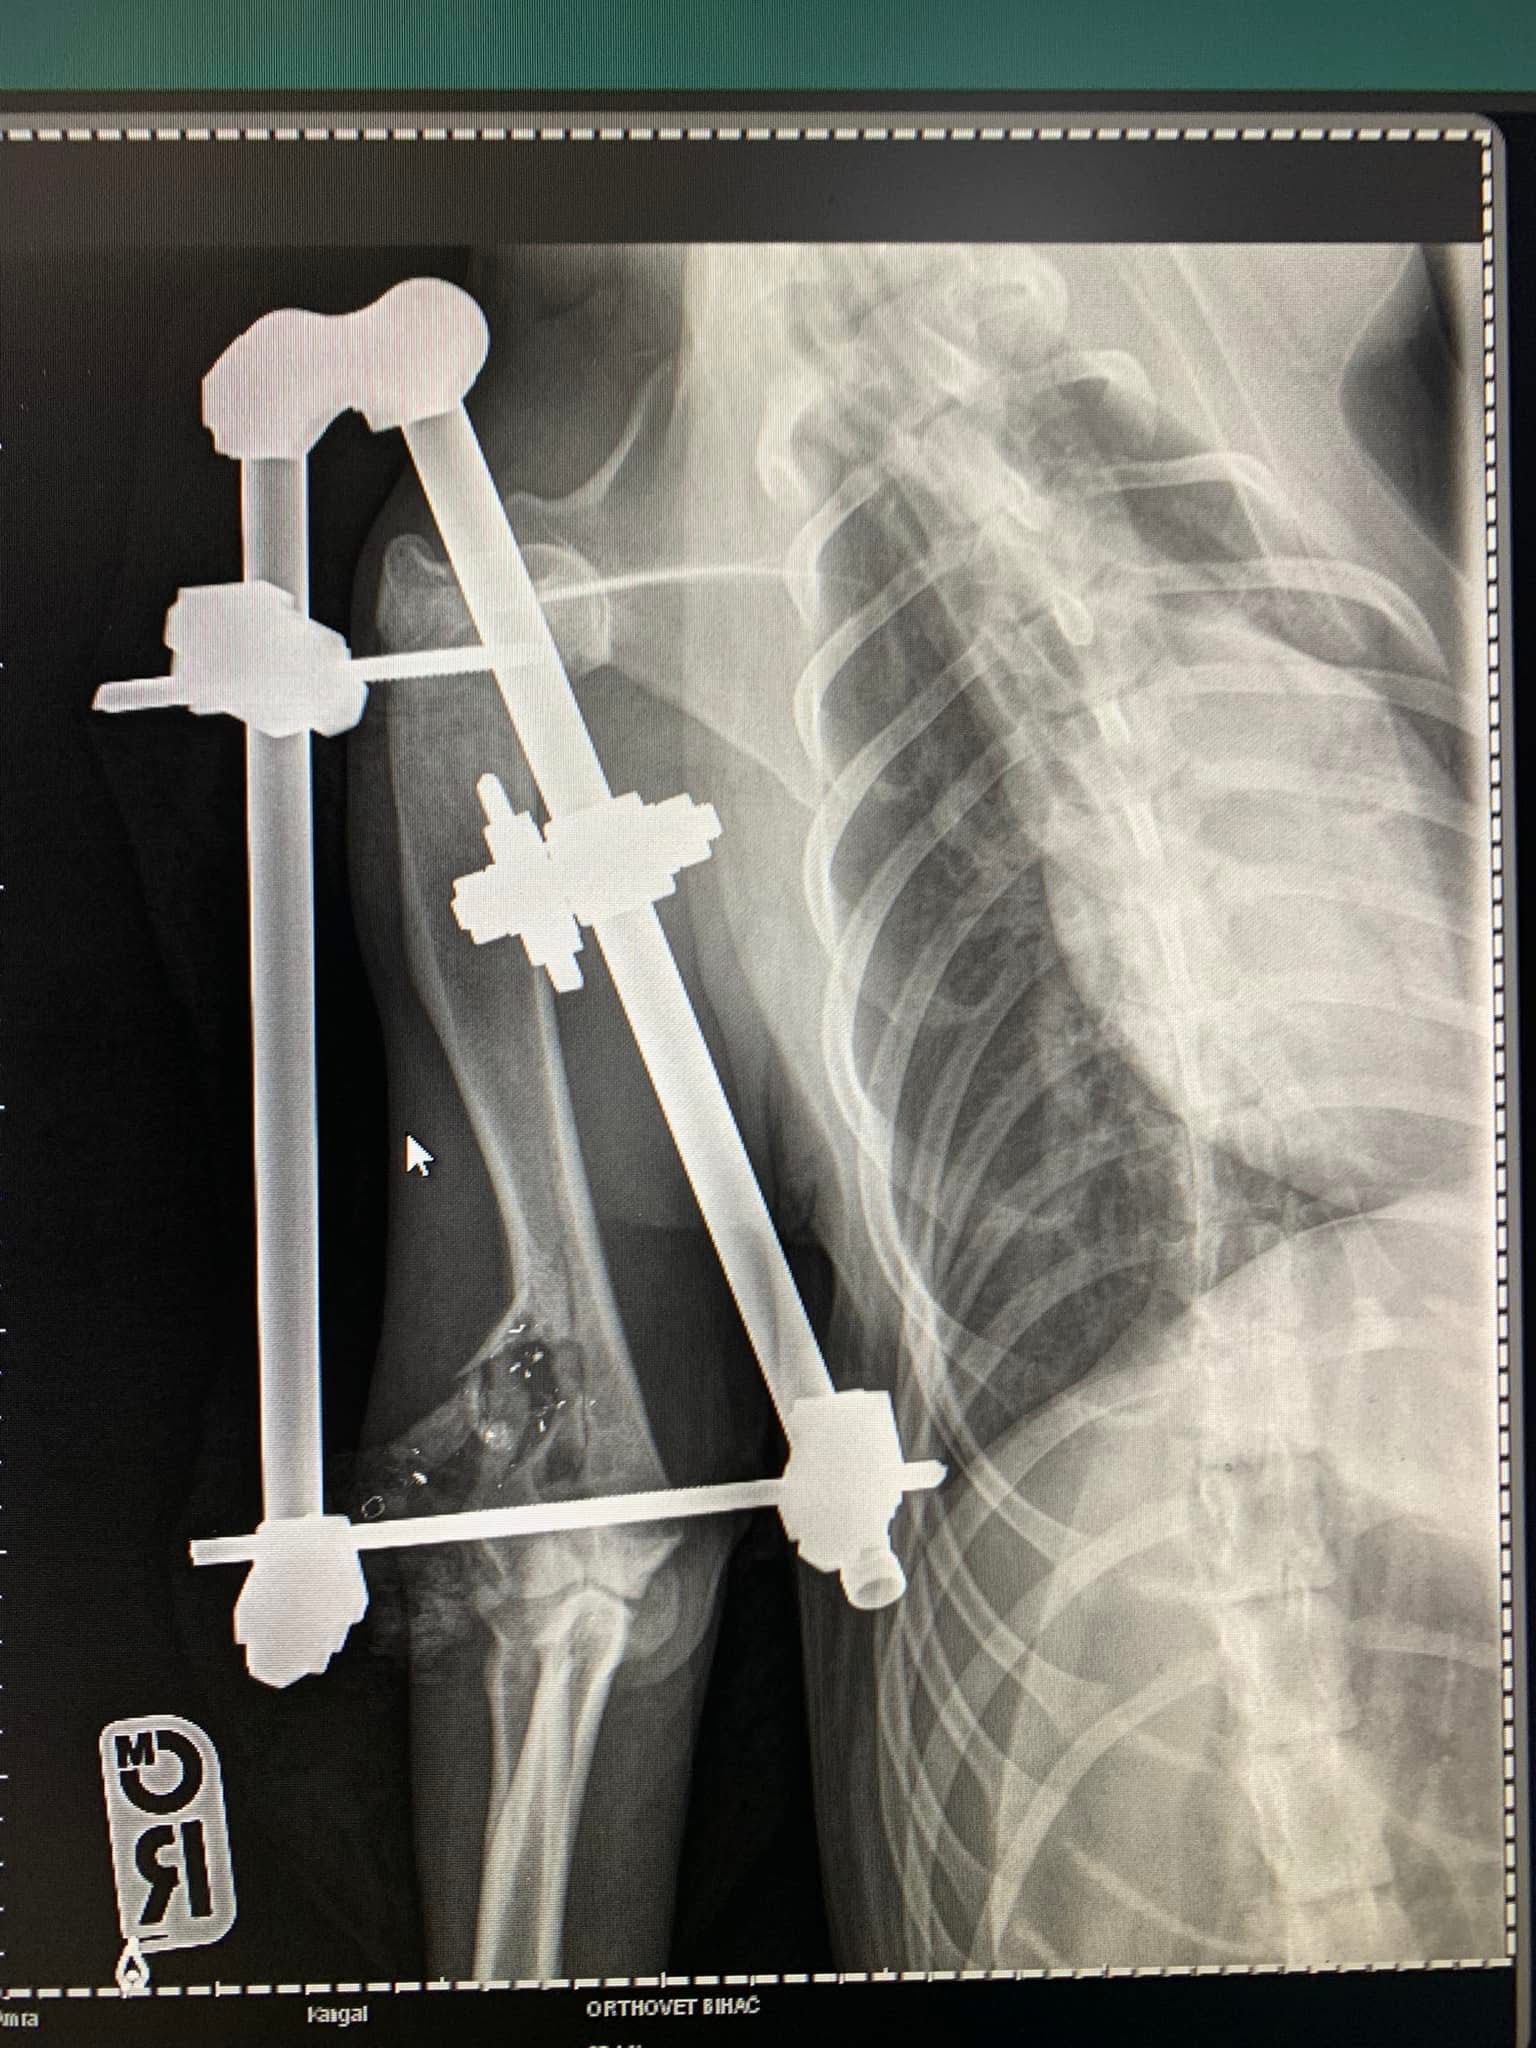

- Liječenje prijeloma kostiju, uključujući intraartikularne frakture

- Hirurške intervencije na zglobovima(artrotomija, artrodeza)

- Korektivne osteotomije za ispravljanje deformiteta